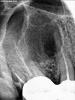

alexpol Опубликовано 30 ноября, 2009 Автор Поделиться Опубликовано 30 ноября, 2009 Сегодня сниму и выложу прицельный снимок 13, 14, 16. выкладываю фото(рентгено) сессию 14 и 16 Ссылка на комментарий

Андрей Опубликовано 1 декабря, 2009 Поделиться Опубликовано 1 декабря, 2009 Понятно что запустил, но надо сейчас делать. Посоветуйте варианты. Заранее благодарен.Patient_name_Alexpol.pdf. Есть свищ. Советуют удаление клыка и 4-ки и постепенное удаление слизистой гайморовой вазухиНе вижу в ситуации никакого криминала. Такие кисты успешно лечатся терапевтически.Вот пример:Ситуация до леченияhttp://content.foto.mail.ru/list/sablinav/fishing/i-101.jpg Ситуация через год после лечения каналов. Киста практически исчезла, несмотря на то, что пациент забил не дальнейшее лечение, проходив с временной пломбой целый год.http://content.foto.mail.ru/list/sablinav/fishing/i-102.jpg Ссылка на комментарий